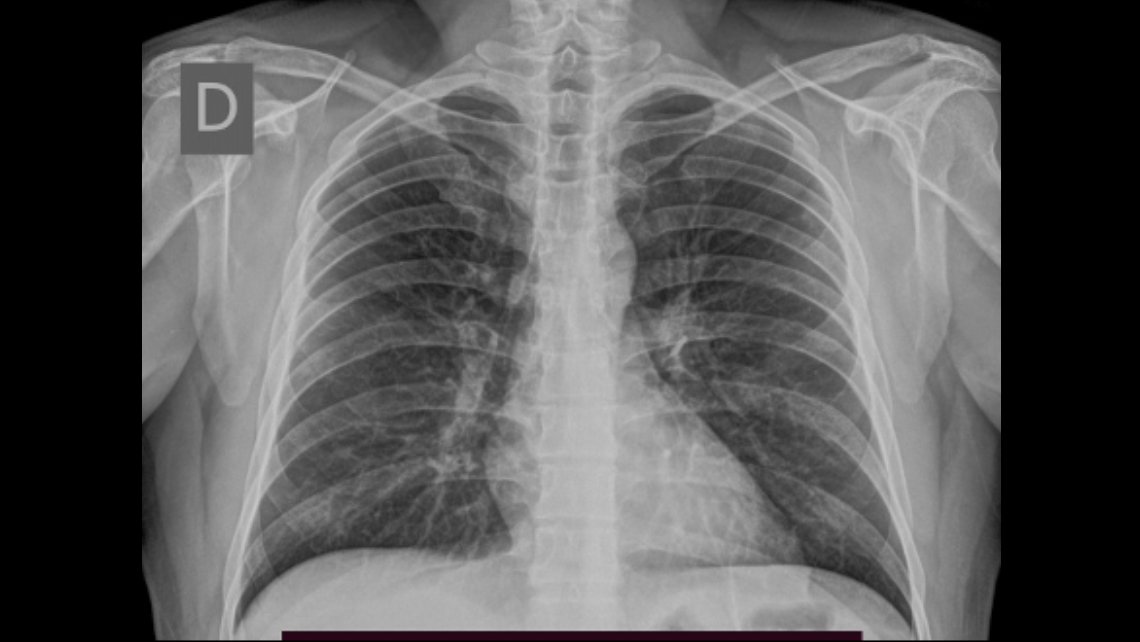

Se trata de paciente masculino de 35 años de edad, con antecedente de neumopatia viral por COVID 19, sin sintomatología respiratoria en la actualidad, que acude al centro de salud por orden de su médico tratante para evaluación médica correspondiente así como exámenes de laboratorio e imágenes.

Se realiza estudio radiológico de tórax en proyección posteroanterior (PA), en el cual se evidencian a nivel del parénquima pulmonar hallazgos de naturaleza residual dado el antecedente referido, el resto del estudio se encontró dentro de los límites normales. Al evaluar los elementos óseos se observa incidentalmente duplicidad de los extremos superior e inferior del cuarto arco costal derecho, en relación a costilla bífida o “en tenedor”.

Las anomalías costales no son frecuentes pero se ven en aproximadamente el 1-2% de las alteraciones óseas observadas en la práctica diaria, en la mayoría de los casos se trata de hallazgos aislados que ocurren en forma esporádica y no tienen representación significativa en la clínica. La costilla bífida o “en tenedor” corresponde a una deformidad congénita focal que representa el 0.6% de estas anomalías, siendo la más frecuente.

En la mayoría de los casos se diagnostica incidentalmente en el estudio radiológico de tórax ya que los pacientes no refieren ninguna sintomatología. Se ha asociado con síndromes genéticos tales como Gorlin-Goltz, síndrome de Jobs y síndrome de Kindler, por ello los pacientes con dicha variante deben ser evaluados con un adecuado examen físico, con especial atención en la cavidad oral y la piel, buscando signos que sugieran algún síndrome genético. Si el examen físico está normal y el paciente está asintomático no serán necesarios estudios de extensión ya que correspondería a un hallazgo aislado sin representación clínica.